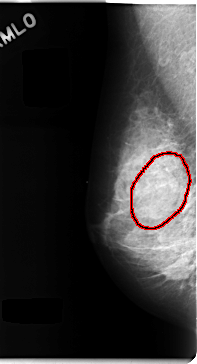

FILE: C_0107_1.RIGHT_MLO.OVERLAY

TOTAL_ABNORMALITIES 1

ABNORMALITY 1

LESION_TYPE MASS SHAPE OVAL MARGINS CIRCUMSCRIBED

ASSESSMENT 3

SUBTLETY 4

PATHOLOGY BENIGN

TOTAL_OUTLINES 1

BOUNDARY